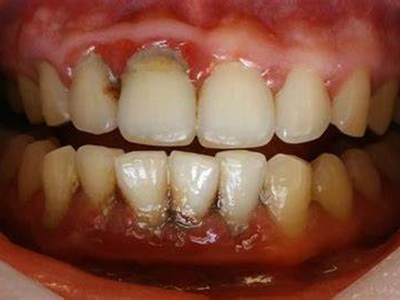

牙龈退缩牙根暴露出现黑斑图

牙龈退缩患者的上排多颗牙齿处的牙龈出现回缩,从而导致牙根外露,外露的牙根上存在黑色的牙菌斑、牙结石,伴有口臭、牙根面敏感等症状。